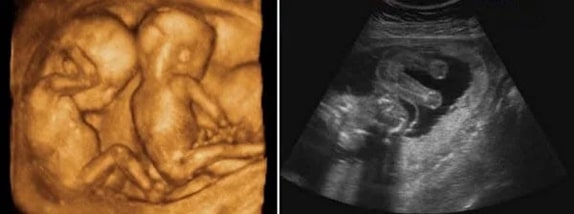

Ayrıca ikiz gebelik ultrason görüntüleri de listemizde bulunmaktadır. Ek olarak, gebelikte bebeğin boyu ve kilosu da kişiden kişiye değişiklik gösterse bile bilgi edinmek için eklenmiştir. Ultrason görüntüleri yazılarından önce isterseniz aşağıdan hamilelikte hafta hafta karın büyümesi galerimize göz atabilirsiniz.

21 Haftalık İkiz Gebelik Ultrason Görüntüleri

22 Haftalık İkiz Gebelik Ultrason Görüntüleri

23 Haftalık İkiz Gebelik Ultrason Görüntüleri

24 Haftalık İkiz Gebelik Ultrason Görüntüleri

25 Haftalık İkiz Gebelik Ultrason Görüntüleri

26 Haftalık İkiz Gebelik Ultrason Görüntüleri

27 Haftalık İkiz Gebelik Ultrason Görüntüleri

28 Haftalık İkiz Gebelik Ultrason Görüntüleri